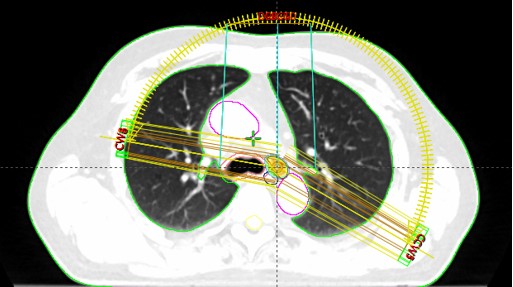

SABR meta mediastini et abdominis (5.5.-25.5.2020.)

lc 40

lc 40 2

lc 40 3

lc 40 4